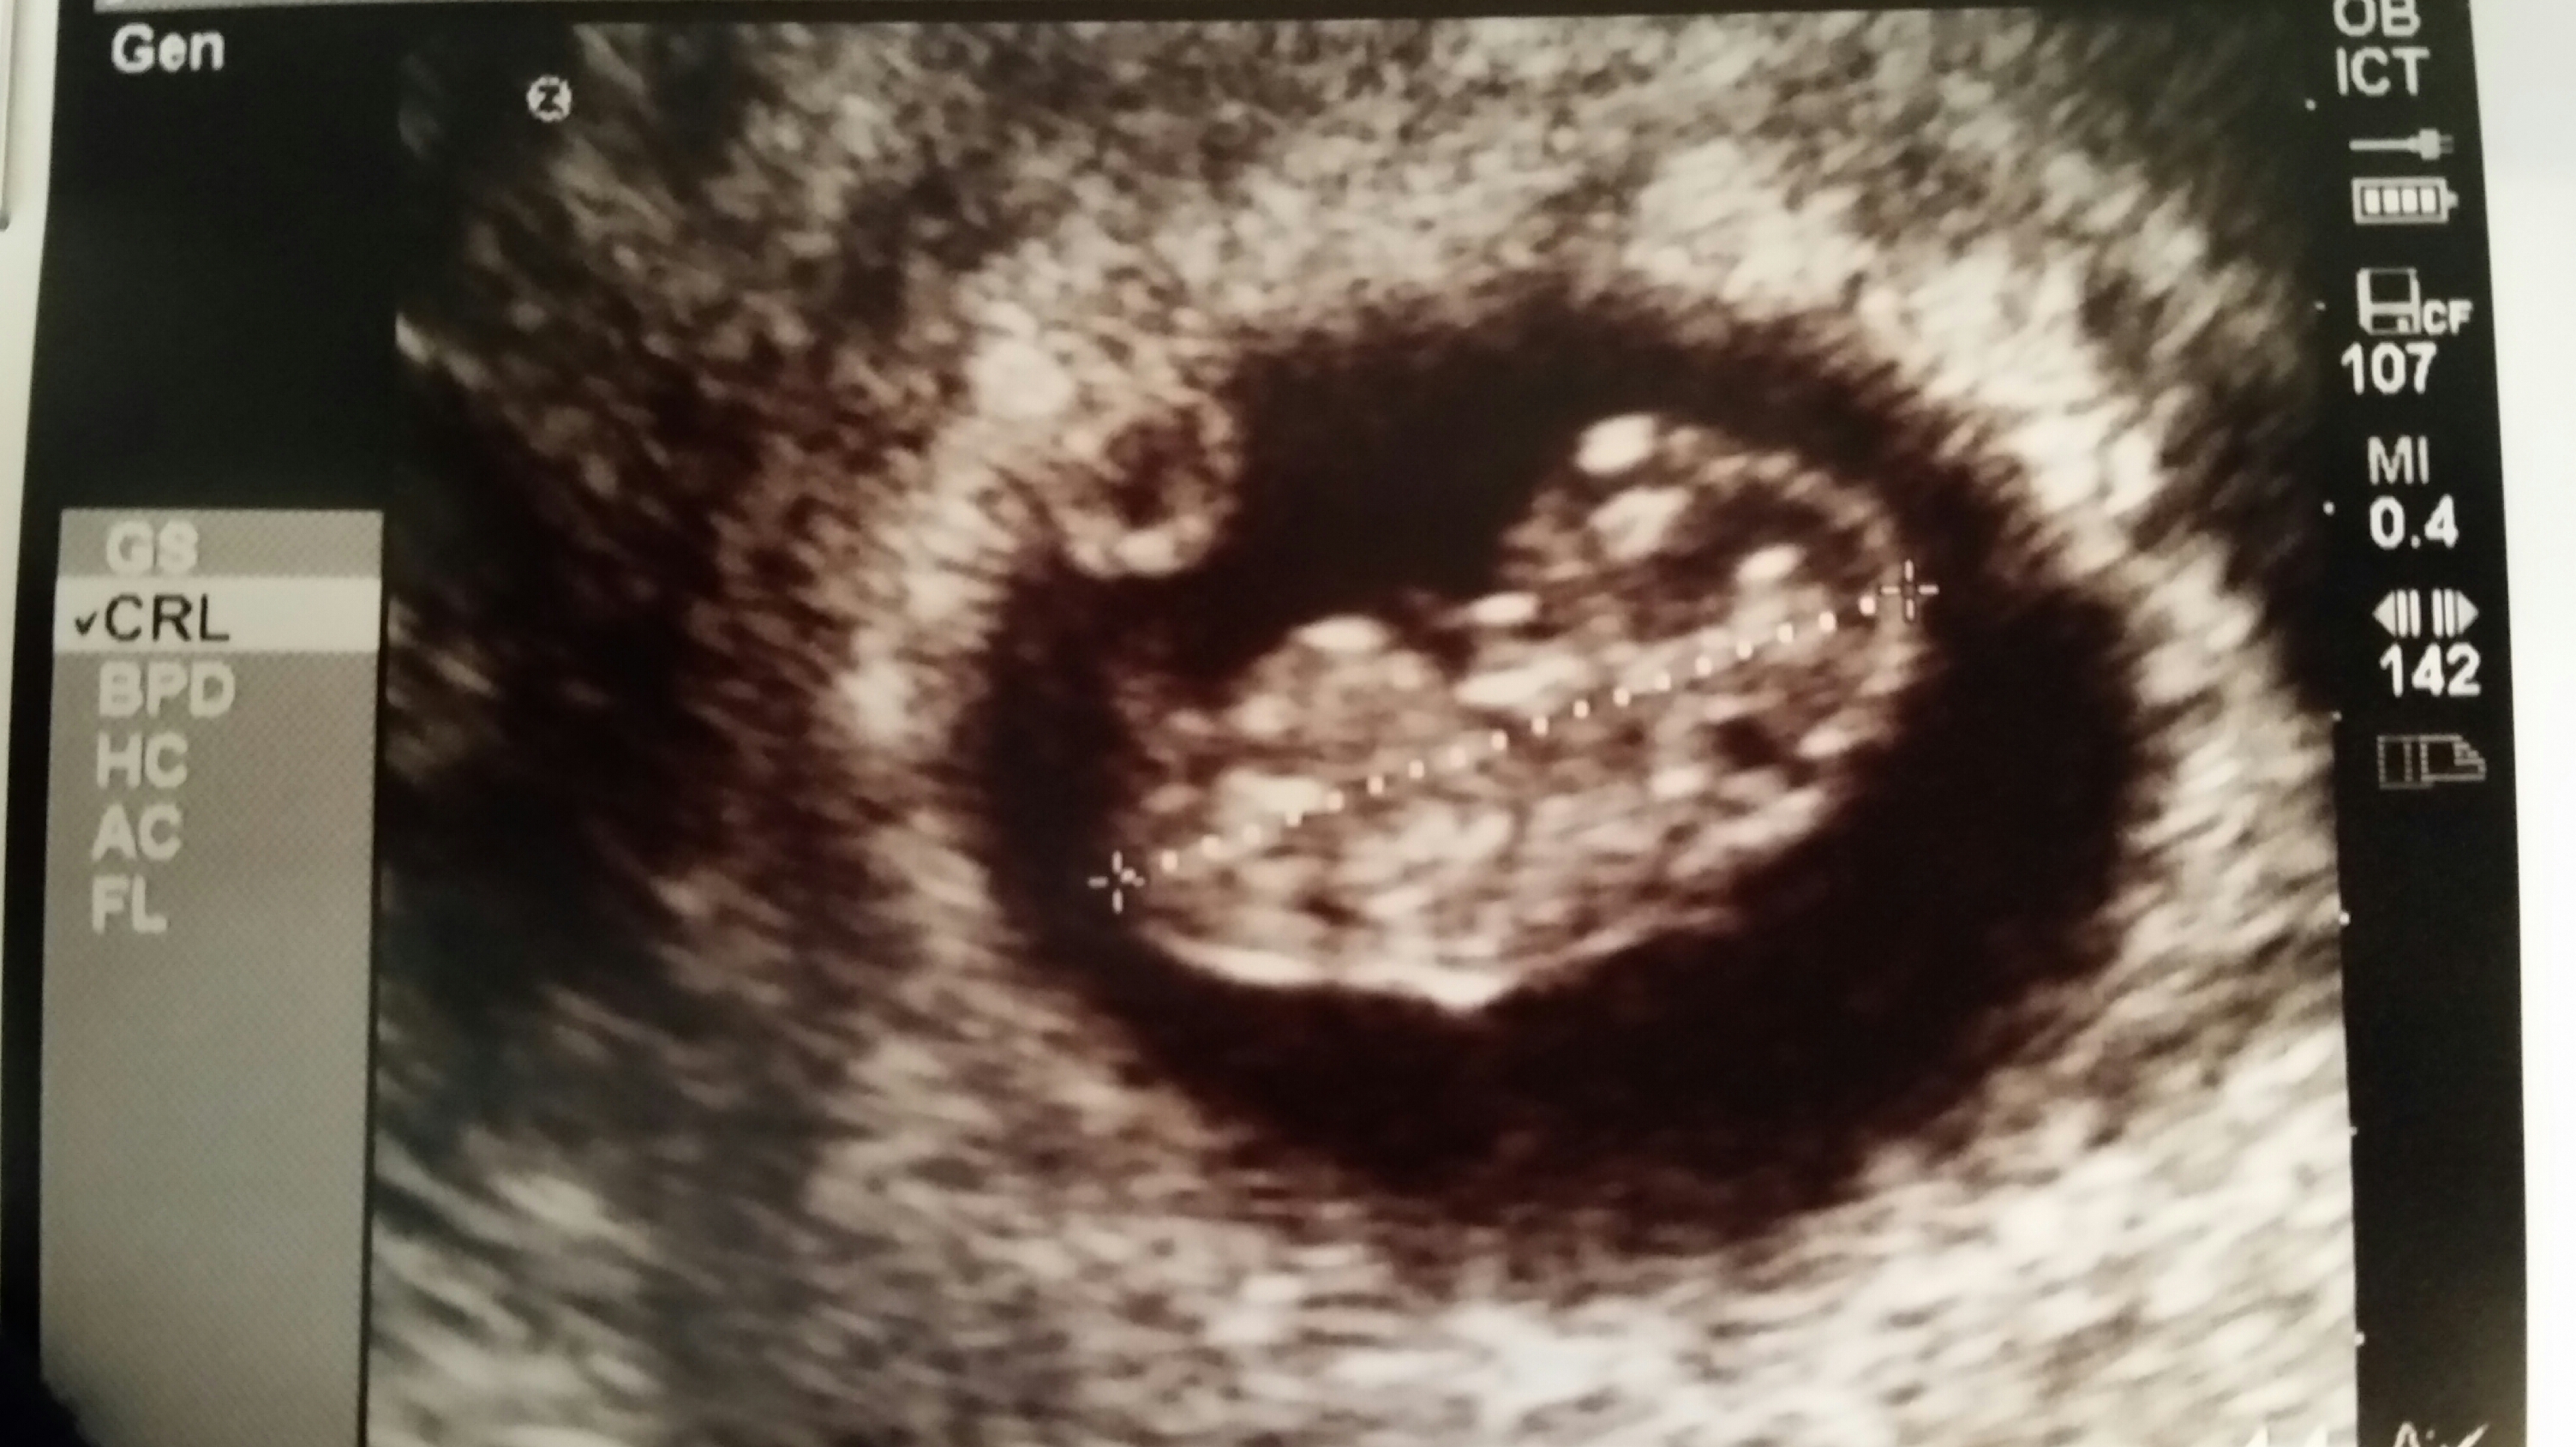

Here is our LO from our dating u/s yesterday (measuring 6w6d then, 7w today). It was so amazing & surreal to see its heart beating. I now fully understand "love at first sight." (So corny, I know lol)